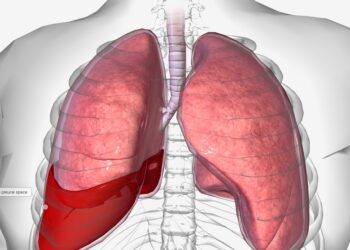

Paveldima hemoraginė teleangiektazija (HHT), dar vadinama Oslerio–Weberio–Rendu sindromu, yra reta genetinė liga, kuri pažeidžia kraujagysles. Šios ligos metu organizme formuojasi...